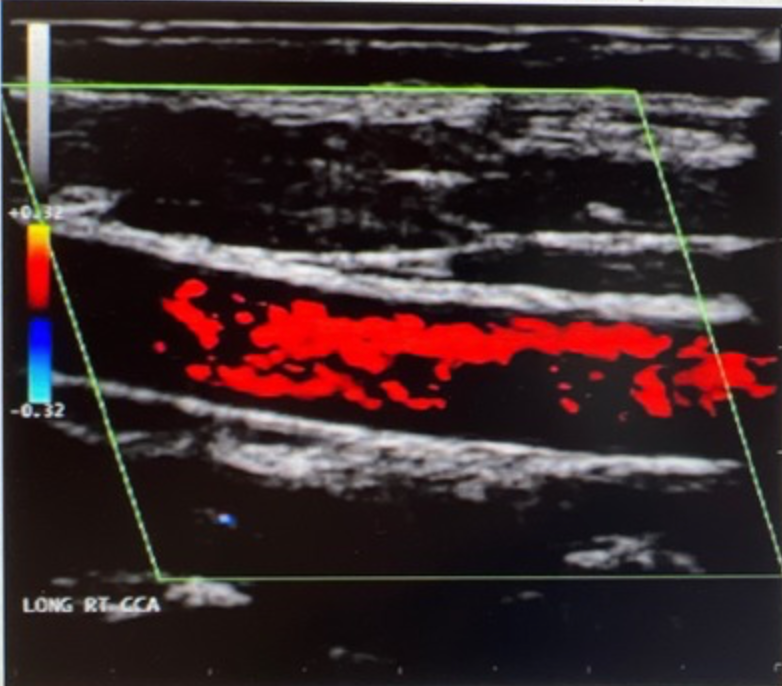

<p>What should be done to adjust and improve the color Doppler displayed on the image?</p><p>a. steer box <br>b. increase PRF <br>c. decrease sample volume<br>d. increase velocity scale</p>

What should be done to adjust and improve the color Doppler displayed on the image?

a. steer box

b. increase PRF

c. decrease sample volume

d. increase velocity scale

decrease sample volume